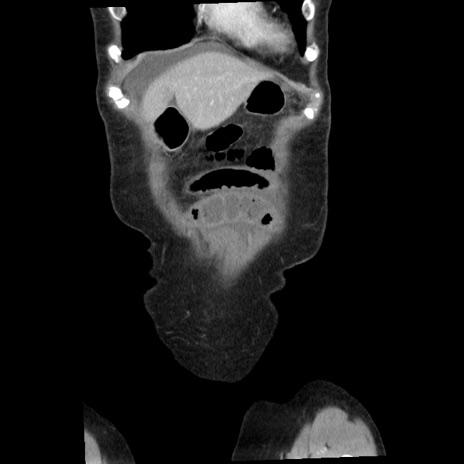

横断像